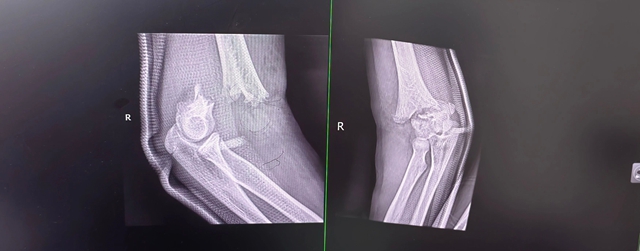

紧急完善影像检查后,诊断结果很快明确:中医诊断为“骨折病(气滞血瘀证)”,当“续筋接骨,活血化瘀”;西医诊断——右肱骨髁上骨折、右桡骨远端骨折,还合并正中神经损伤。

右肘关节肿胀得厉害,明显变了形,皮肤上还散着青紫瘀斑和水泡,一碰就疼,轻轻活动,疼痛更甚,甚至能感触到骨头摩擦的声音;右腕关节同样肿胀,活动疼痛,症状与肘关节如出一辙,腕部呈轻微下垂状态,想往上抬都没力气,手指麻木感和伴有食指屈曲活动障碍也始终没有缓解。